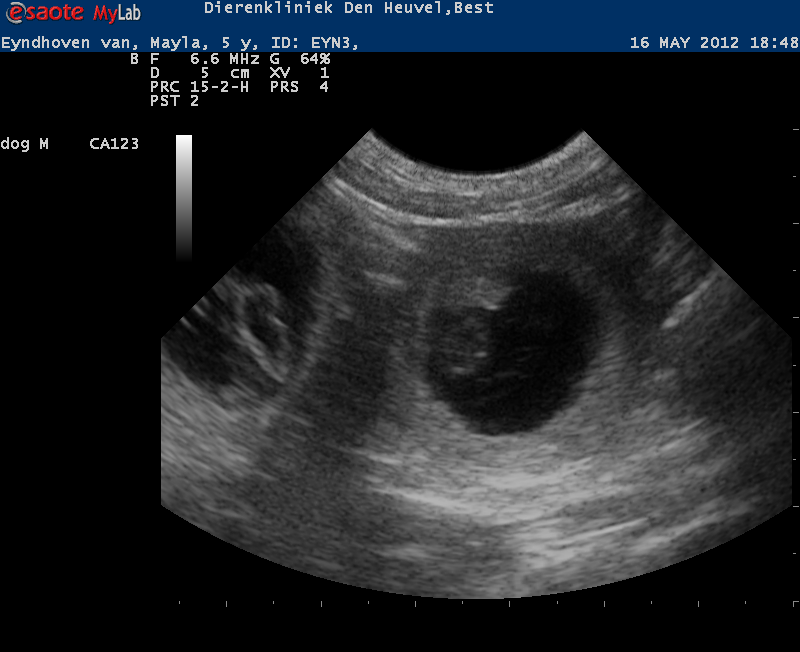

2012-05-16

YES, Mayla is pregnant!

Mayla is doing great. Her weight is 16,6 kg and her belly is 56 cm.